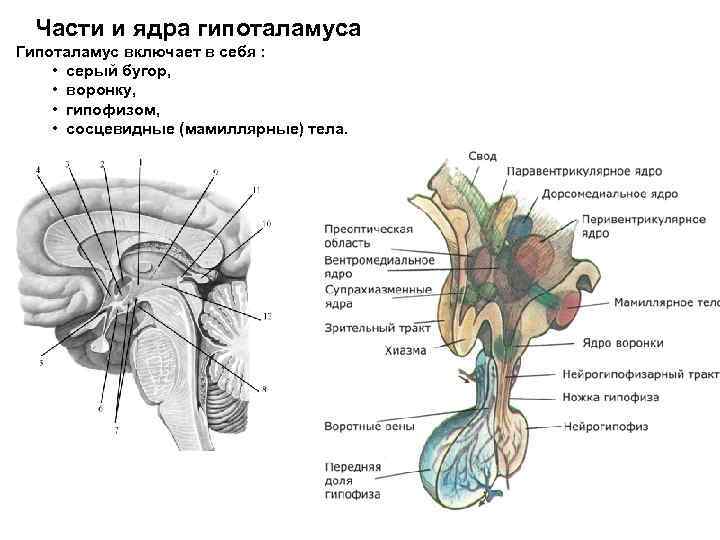

Как работает центр насыщения в гипоталамусе: визуальные иллюстрации